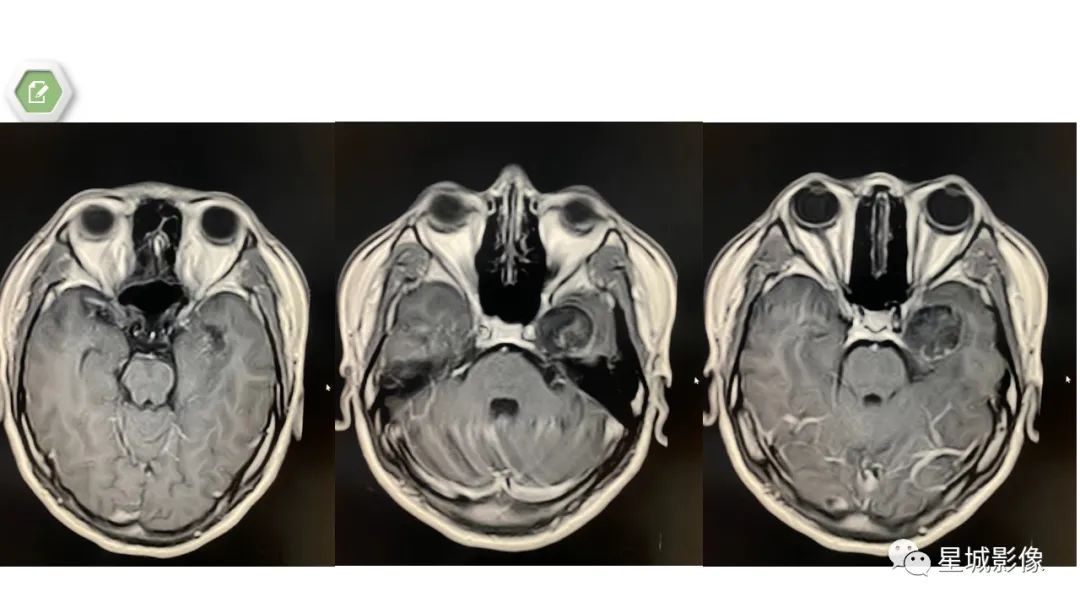

【病例】颅内成熟性囊性畸胎瘤1例MR影像表现-1